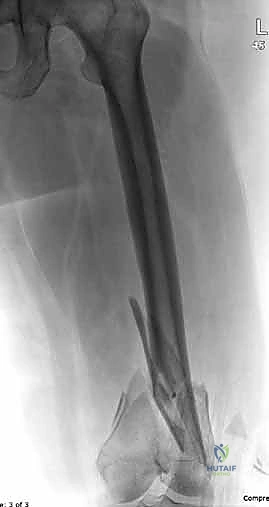

المرحلة الرابعة: التثبيت النهائي بالشرائح والمسامير (Fixation)

يتم استخدام "شرائح الإغلاق التشريحية" (Anatomical Locking Plates) المصنوعة من التيتانيوم عالي الجودة. هذه الشرائح مصممة خصيصاً لتأخذ شكل الجزء السفلي من عظم الفخذ. يتم تمرير الشريحة أسفل العضلات وتثبيتها بمسامير تغلق داخل الشريحة نفسها (Locking Screws)، مما يوفر ثباتاً ميكانيكياً هائلاً، حتى في حالات العظام الهشة.

في بعض الحالات المعقدة جداً، قد يتطلب الأمر استخدام شريحتين (Dual Plating) لضمان عدم تحرك الكسر أثناء فترة التعافي.

المرحلة الخامسة: الإغلاق التجميلي

بعد التأكد التام من استقرار الكسر وحركة المفصل عن طريق الأشعة داخل غرفة العمليات، يتم إغلاق الجرح بطبقات متعددة باستخدام خيوط تجميلية لتقليل الندبات، ووضع أنبوب تصريف (Drain) لمنع تجمع الدم.